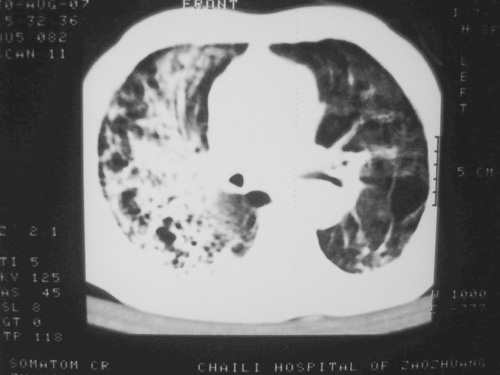

老年男性,70岁。煤矿工人20年。一周前咳嗽、发烧,拍x片考虑矽肺可能。始终咳嗽行ct检查,发现弥漫性病变,似感染但密度很高,细支气管肺泡癌无法排除,请老师给予指点。

一般矽肺多为双肺融合状,团块状高密度结节影.并散在多处小结节影.可这个病人只表现在单肺,并没有融合结节影.一周前的x片没显示大片高密度影,可定位扫描时(图象忽略传了),右肺已经清晰显示大片高密度影.作比较感觉是新病灶.可实际表现又不象,所以才拿来让各位老师看看.

矽肺,两肺间实质炎症,蜂窝肺。

矽肺  两肺间质性炎症伴纤维化(蜂窝肺)

矽肺合并右肺结核可能性大.右侧少量胸腔积液.

ct片与平片只相隔1周时间变化太大,结合临床应该首先考虑尘肺合并感染,肺泡癌变化不会这么快,